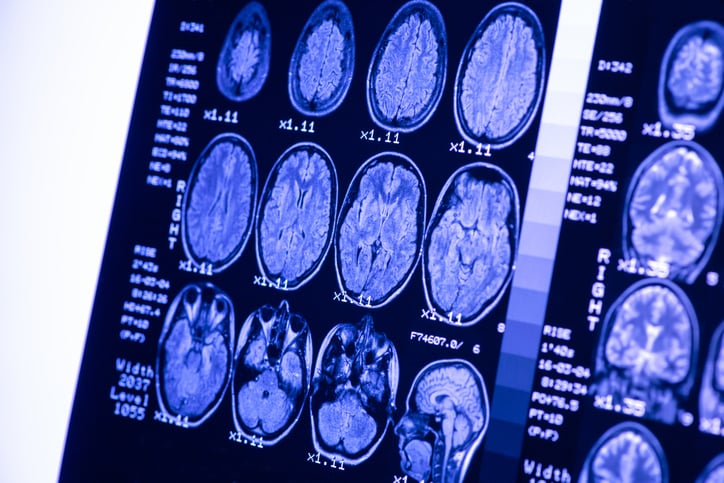

Il glioblastoma, appartenente ai tumori della famiglia dei gliomi, è la neoplasia a carico del cervello più difficile da curare. Si tratta di una malattia che colpisce prevalentemente le persone dopo i 50 anni. Purtroppo, nonostante le terapie, solo il 25% dei pazienti è vivo ad un anno dalla diagnosi e circa il 5% a 5 anni. Ciò accade perché il glioblastoma, anche quando operato in tempo, presenta tassi di recidiva molto elevati. Non solo, quando il tumore si ripresenta è spesso resistente alle terapie. Una delle caratteristiche che rende questo tumore particolarmente difficile da curare, specialmente nella recidiva, è la sua capacità di assumere caratteristiche simili ai neuroni. Una peculiarità che rende il glioblastoma difficile da trattare anche con i più moderni farmaci immunoterapici.

Nello studio da poco pubblicato, realizzato dalla dottoressa Simona Migliozzi, gli scienziati hanno provato ad analizzare i meccanismi che le cellule di glioblastoma mettono in atto per somigliare ai neuroni e sfuggire all'effetto delle terapie. Per farlo hanno adottato un metodo unico: anziché analizzare il Dna tumorale gli autori hanno confrontato il proteoma -ovvero l'espressione di tutte le proteine della cellula e loro relative modificazioni- di 123 campioni tumorali di glioblastoma con il proteoma di un tessuto sano. Dalle analisi gli scienziati hanno scoperto che c'è una grossa differenza nell'espressione delle proteine tra il glioblastoma primario e le cellule di glioblastoma in recidiva e resistenti ai farmaci. Ed è proprio dentro questa differenza che c'è la chiave per cercare di evitare che il tumore diventi resistente.